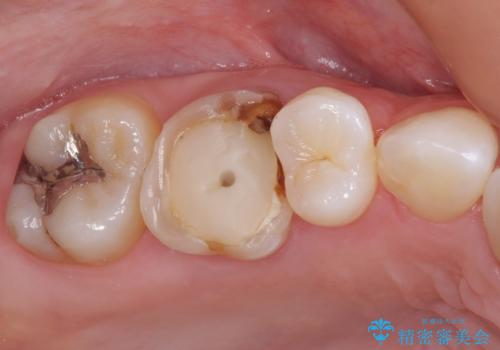

- 虫歯により神経を取り除いた前歯の変色が気になるとのことで来院された患者様です。

レントゲン写真より、歯根の炎症が認められなかったため、ファイバーコアによる土台築製後、オーダーメイドタイプのオールセラミッククラウンにて補綴することとしました。